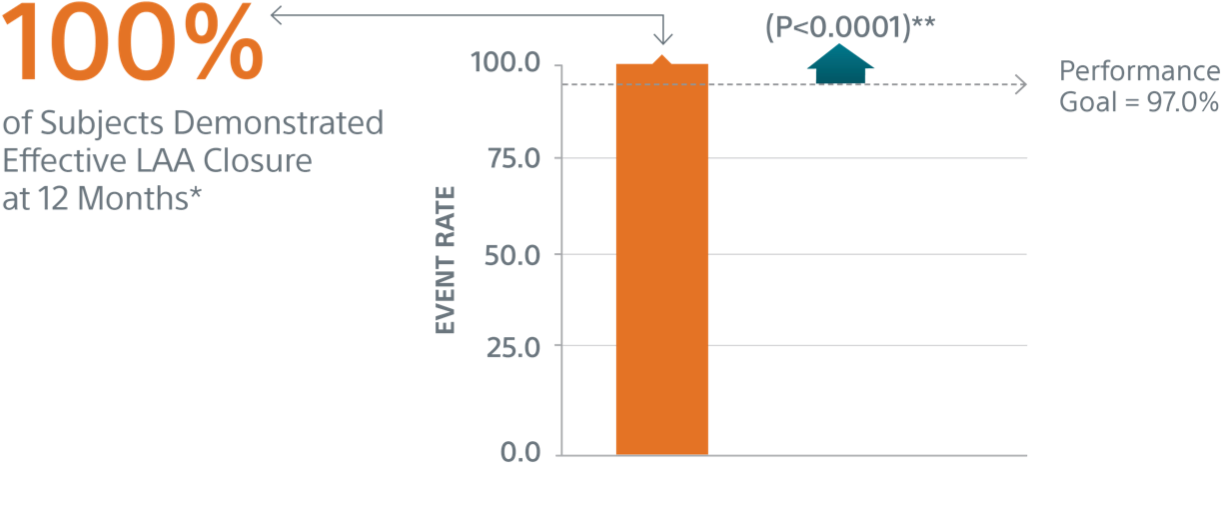

- Primary Efficacy Endpoint: The rate of effective LAA closure defined as any peri-device flow ≤5mm demonstrated by TEE at 12 months

Primary Efficacy Endpoints

The rate of effective LAA closure defined as any peri-device flow ≤5mm demonstrated by TEE at 12 months.

** Performance goal pased on the rates observed in PREVAIL(1) and CAP2(2), minus a clinically relevant delta